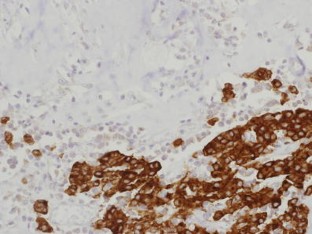

Fig 1